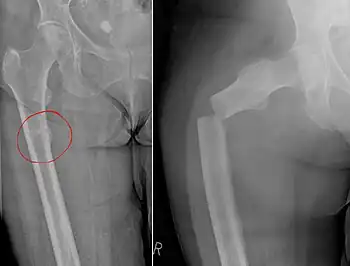

| Chalkstick fracture due to bone metastasis of breast cancer. Left image shows the metastasis, on the right a pathological fracture a few days later. | |